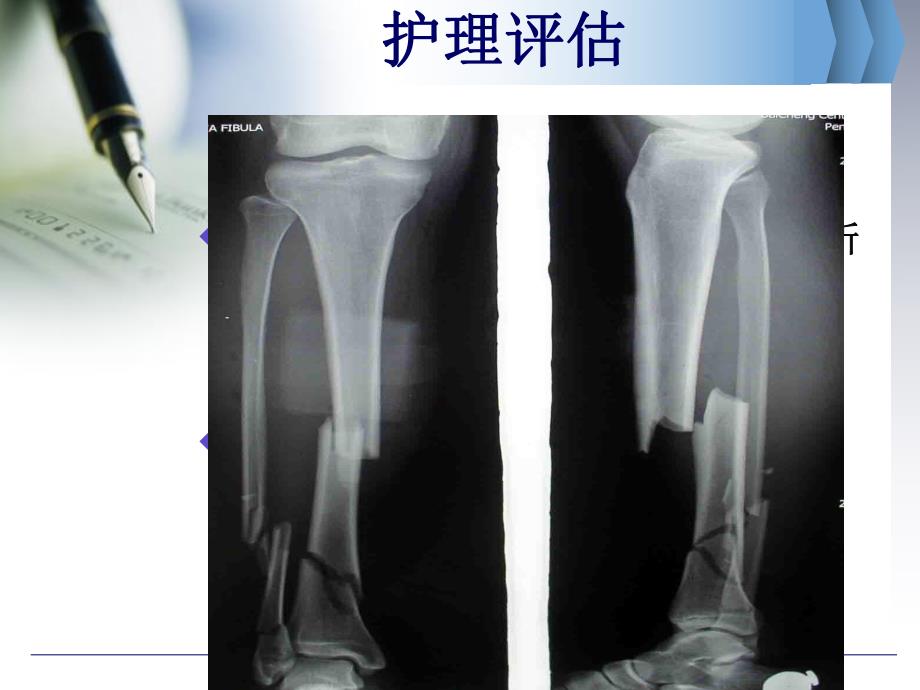

1、胫胫腓腓骨开放性粉碎性骨开放性粉碎性骨折护理骨折护理查房查房 病情介绍病情介绍 患者男,患者男,49岁,于岁,于2013-12-14因因车祸致右小腿受伤,伤后右小腿远端车祸致右小腿受伤,伤后右小腿远端内侧见一开放性创口,远端外翻畸形,内侧见一开放性创口,远端外翻畸形,剧烈疼痛,失血量不详,伤后无昏迷,剧烈疼痛,失血量不详,伤后无昏迷,无恶心、呕吐,无四肢湿冷、脉搏细无恶心、呕吐,无四肢湿冷、脉搏细数,无胸腹闷痛。急诊以数,无胸腹闷痛。急诊以“右胫腓骨右胫腓骨开放性粉碎性骨折开放性粉碎性骨折”收住入科,并于收住入科,并于当日送手术室行右胫腓骨开放性粉碎当日送手术室行右胫腓骨开放性粉碎性骨折切开复

2、位内固定术,术后予以性骨折切开复位内固定术,术后予以抗炎、抗凝、护胃、活血化淤等对症抗炎、抗凝、护胃、活血化淤等对症治疗。治疗。护理评估护理评估u粉碎性骨折:粉碎性骨折:骨碎裂成骨碎裂成3块以上。骨折块以上。骨折线成线成T形或形或Y形,故又称形,故又称T形或形或Y形骨折形骨折u开放性骨折:开放性骨折:骨折部位的皮肤或粘膜骨折部位的皮肤或粘膜破裂,骨折断端直接或间接与外界相通破裂,骨折断端直接或间接与外界相通概念:病病 因因直接暴力直接暴力(打击、撞击、车轮碾压等打击、撞击、车轮碾压等)间接暴力间接暴力(高处坠落、滑倒高处坠落、滑倒)护理评估护理评估初步判断初步判断进一步判断进一步判断有无生命威